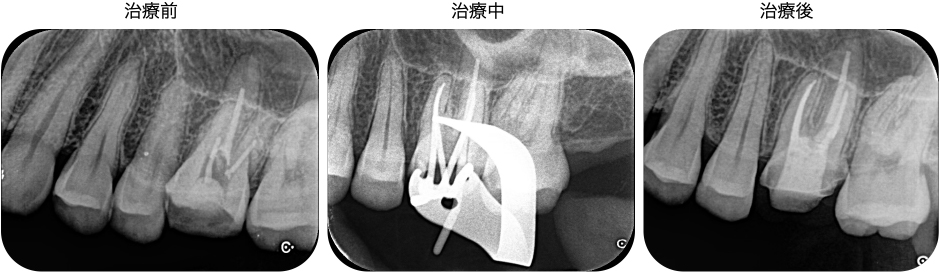

すでに根管充填(根管治療後に根の中を封鎖するつめもの)が行われていましたが、以下の点で問題がある状態でした。

・形成されているにもかかわらず根管充填が不十分な部位が多い

・MB2(隠れた根管)がおそらく手づかずの状態

・虫歯がまだ少し残っている

以上のことから、根管内の細菌は未だ多く残存しており、精密な根管治療によってさらなる細菌の減少が期待できる状態でした。初診来院時には検査と今後の治療のご説明を行い、2回目から根管治療を開始していくことになりました。

根管治療

2回の治療で根管治療は完了しました。根管治療完了時には、元に感じていた痛みはかなり軽減し、少し響く程度になりました。このまま6〜12ヶ月の経過観察となります。